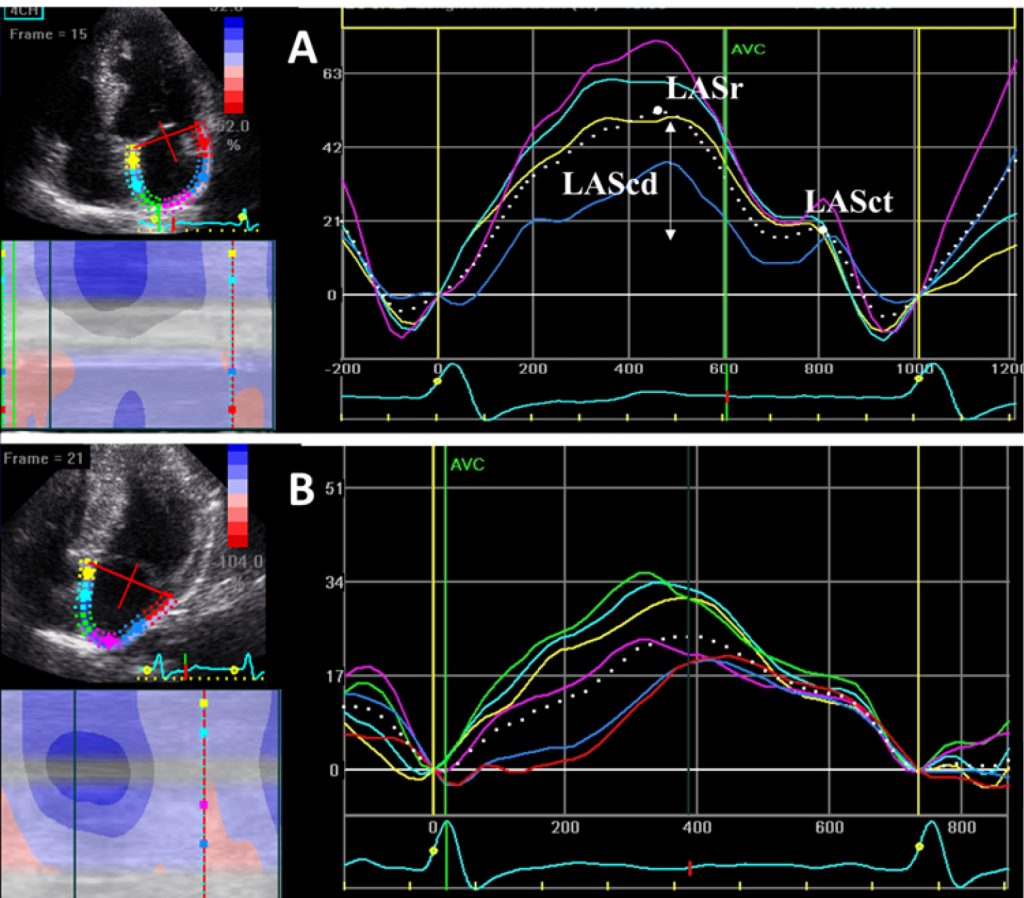

Two-dimensional speckle tracking-derived longitudinal LA function was acquired from apical views in 60 HCM patients, 60 HTN patients, and 34 age-matched controls. HCM patients also underwent CMR, with measurement of late gadolinium enhancement (LGE) extension. Association with LA strain parameters was analyzed. Statistical significance was set at p<0.05.

Mean LV ejection fraction was not different between the groups. The E/e’ ratio was impaired in the HCM group and preserved in the control group. LA mechanics was significantly reduced in HCM, compared to the HTN group. LA strain rate in reservoir (LASRr) and in contractile (LASRct) phases were the best discriminators of HCM, with an area under the curve (AUC) of 0.8, followed by LA strain in reservoir phase (LASr) (AUC 0.76). LASRr and LASR-ct had high specificity (89% and 91%, respectively) and LASr had sensitivity of 80%. A decrease in 2.79% of LA strain rate in conduit phase (LASRcd) predicted an increase of 1cm in LGE extension (r2=0.42, β 2.79, p=0.027).

LASRr and LASRct were the best discriminators for LVH secondary to HCM. LASRcd predicted the degree of LV fibrosis assessed by CMR. These findings suggest that LA mechanics is a potential predictor of disease severity in HCM.